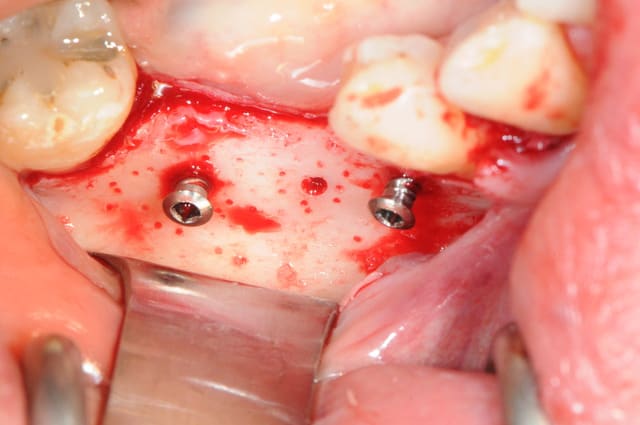

photo

1: foret de perçage pour que l'os puisse apporter du sang.

(initialement, c'est un foret pour les pins densply)

2-3: je fais des petits trous (comme Serge)

4: la boite avec toutes les vis (différentes tailles)

5-6: le foret de mise en place des vis et le foret destiné à faire un pré-perçage

7-8: et voilà 3 vis qui vont maintenir ma membrane au dessus de l'os.

9-10-11: la membrane maintenue par deux pins sur la table interne osseuse, comblement osseux recouvrant les têtes des vis puis je rabat la membrane que je fixe sur la table osseuse externe